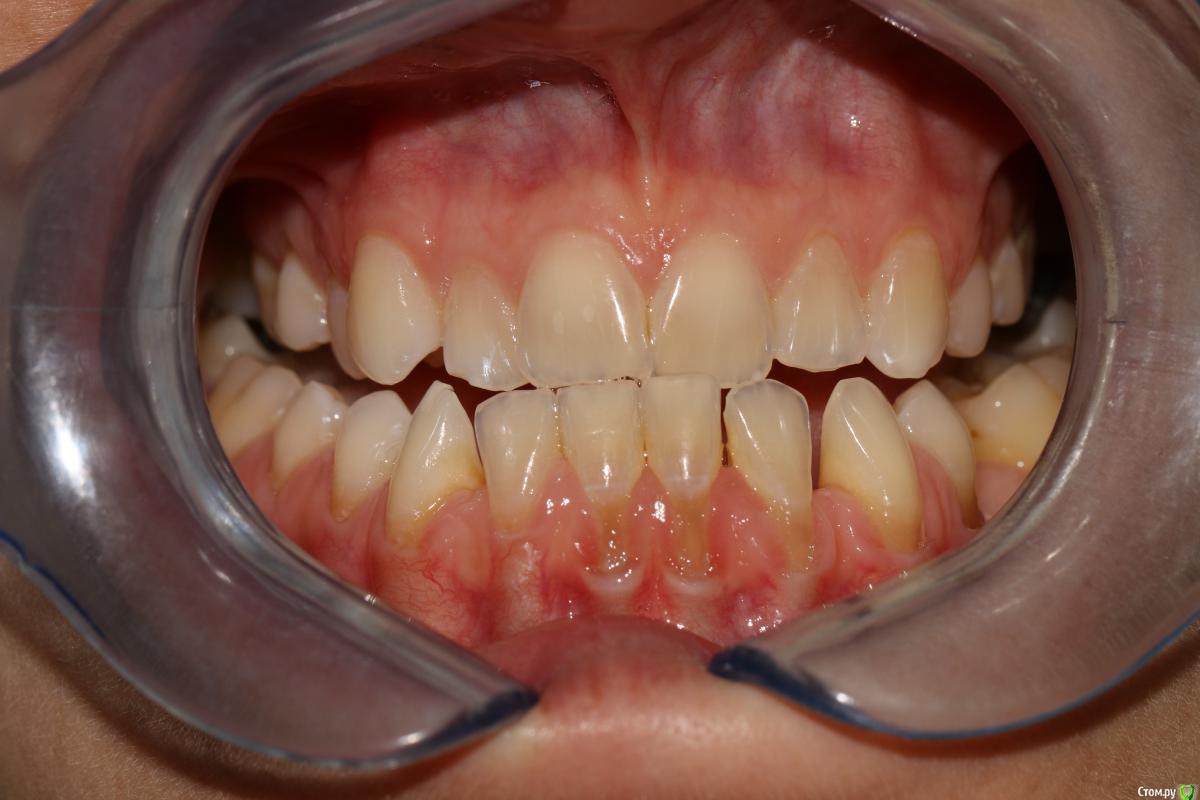

rytovst Опубликовано 15 сентября, 2018 Поделиться Опубликовано 15 сентября, 2018 Здравствуйте ,коллеги!Посоветуйте ,как и чем лучше закрыть данные рецессии перед ортодонтическим лечением.Склоняюсь к расщепленному лоскуту и ССТ с неба + коронально-смещенный лоскут . Может быть взять ССТ с эпителиальной полоской? Ссылка на комментарий

Дмитрий Л. Опубликовано 16 сентября, 2018 Поделиться Опубликовано 16 сентября, 2018 Скажите пожалуйста, а это фото в прикусе...? Какой тут ортодонт диагноз поставил и что планирует делать? Пластика десны перед ортодонтией не всегда показана. Ссылка на комментарий

rytovst Опубликовано 16 сентября, 2018 Автор Поделиться Опубликовано 16 сентября, 2018 -фото ,как вы видите ,не в прикусе ( 6 зубы не смыкаются) -дистальная дизокклюзия - произвести протрузию на нч Ссылка на комментарий

Irouil Опубликовано 16 сентября, 2018 Поделиться Опубликовано 16 сентября, 2018 зачем тогда спрашивать, если сделаете, как нравится?Скейлинг + ЭДТАМожет коллега с Вас пример берет: уже все сделал, а спрашивает из спортивного интереса?) Я бы тоже в резцах шел с эпителием и туннель, в клыках/премолярах может полностью деэпителизировать (если не одним трансплантатом брать будете). В этом случае, имхо, показания к пародонтологии даже без ортодонтии Ссылка на комментарий

Дмитрий Л. Опубликовано 16 сентября, 2018 Поделиться Опубликовано 16 сентября, 2018 В этом случае, имхо, показания к пародонтологии даже без ортодонтии Я не об этом. Если резцы планируется сдвинуть дистально, то рецессия может уменьшится уже уже от этого, соответственно и успех хирургии будет выше после ортодонтии, а не до. - произвести протрузию на нч Вот честно я не понял здесь вас( Вообще здесь не рецессия, а пародонтит. И устранить нужно причину. Уздечка, преддверие...?+1 за туннель и не уверен по поводу коронарного смещения лоскута: риск порвать лоскут + натяжение от губы только увеличится. Ссылка на комментарий